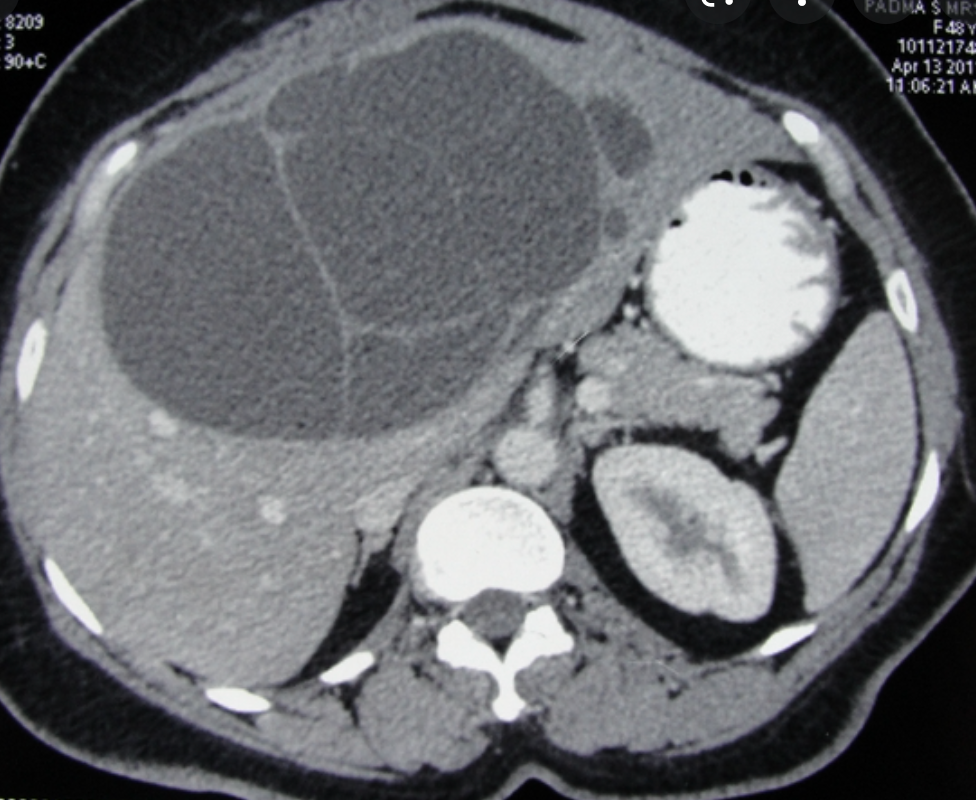

what is this?

Biliary cystadenoma

- uncommon, multilocular cystic liver mass that originates in the bile duct and usually occurs in the right hepatic lobe.

- Typically occurs in women

- h/o chronic abdominal pain

- it may represent a congenital anomaly of the biliary anlage

- COMPLICATIONS

- Malignant transformation cystadenocarcinoma occurs

- IMAGING FEATURES

- well defined and cystic

- internal sepations

- The cyst walls and any other soft tissue components typically enhance with contrast

- variable appearance on MRI depending on the protein content of the fluid and the presence of an intracystic soft tissue component.